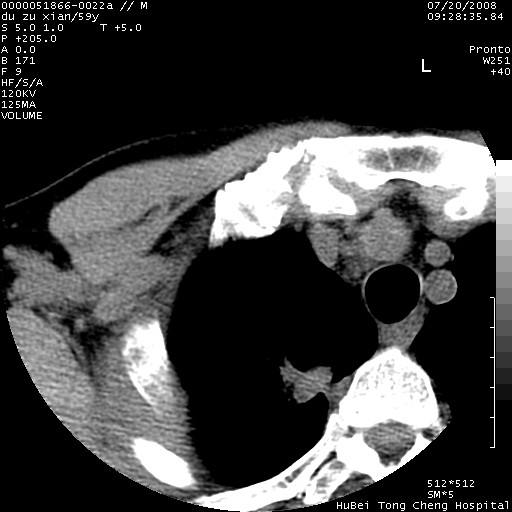

以下是引用宇宙ct在2008-8-25 23:21:00的发言:[br]右肺周围性肺癌并肋骨转移,纵隔淋巴结转移。

以下是引用zsl6918在2008-8-25 22:40:00的发言:[br]右肺周围性肺癌并肋骨转移,纵隔淋巴结转移。

以下是引用zy_zj在2008-8-26 15:24:00的发言:[br]单从病变本身,我倾向良性炎性病变,但肋骨转移了,所以说是考虑右肺周围性肺癌并肋骨、纵隔淋巴结转移可能性大。